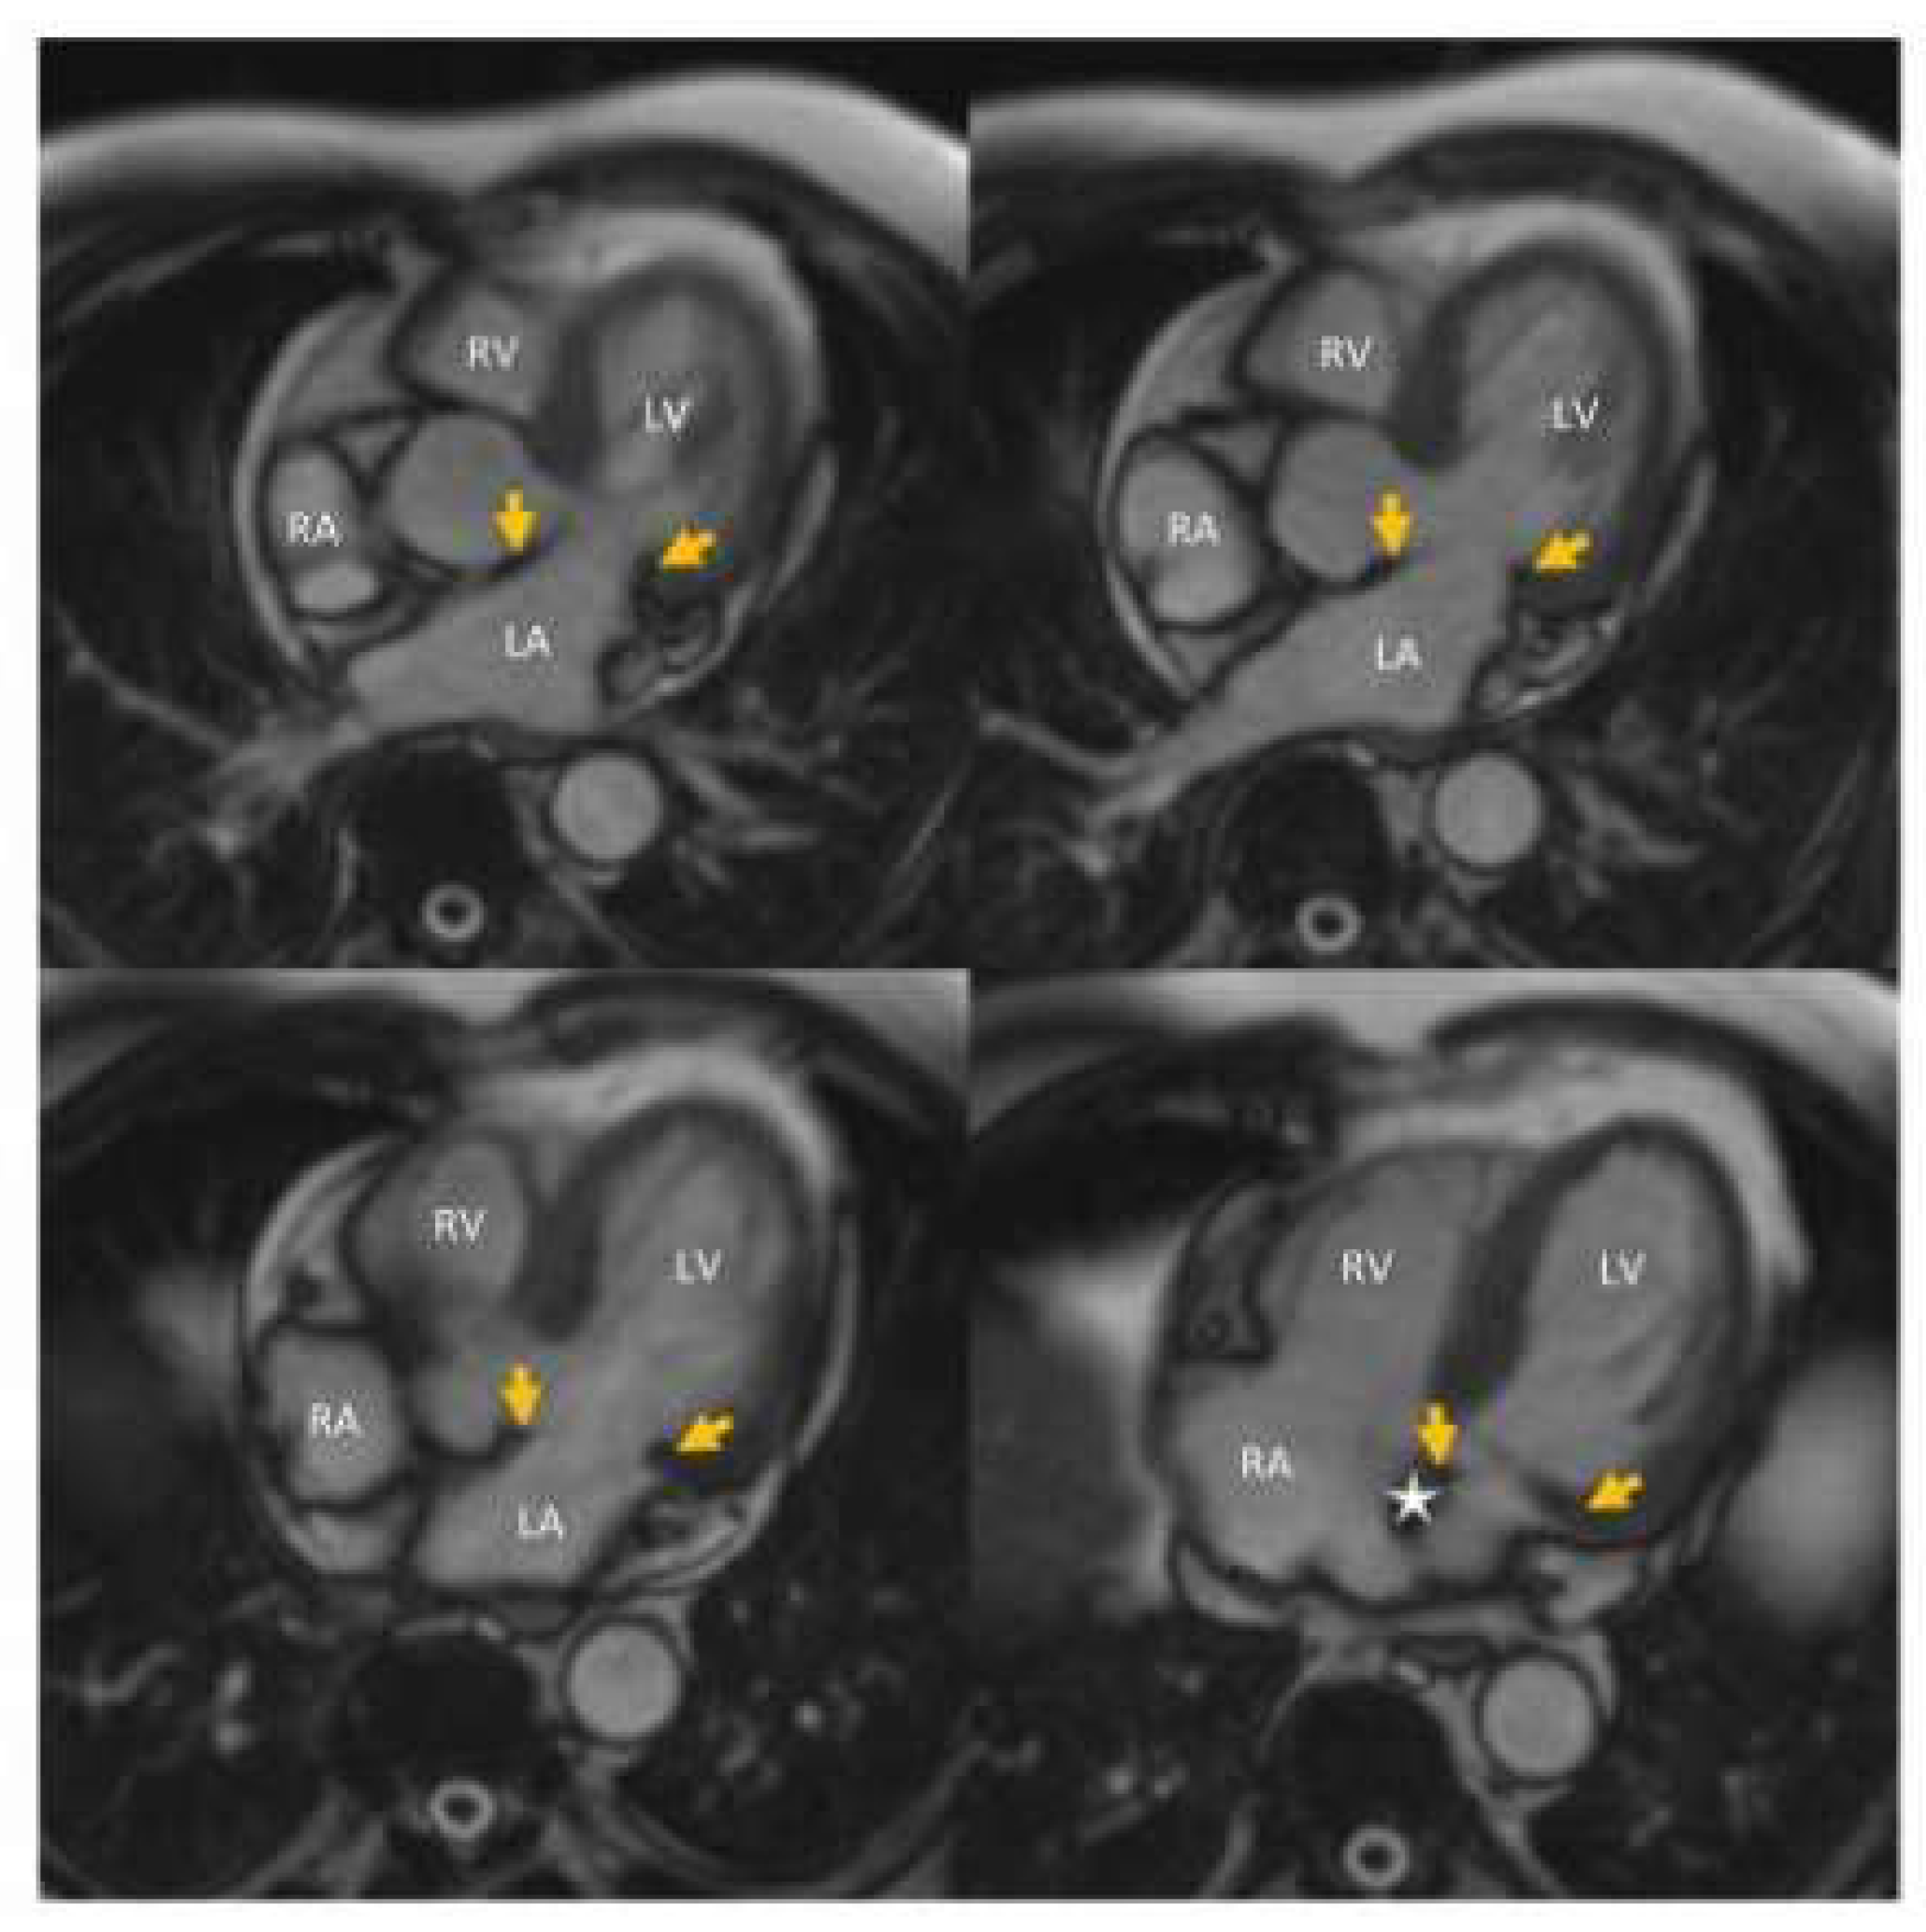

5.1. Case